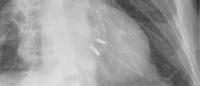

The trial enrolled 614 heart failure patients with moderate-to-severe or severe secondary MR at 78 sites in the United States and Canada who remained symptomatic despite treatment with recommended medical therapies. Participants were randomized to treatment with MitraClip–a minimally invasive treatment that fastens the mitral valve leaflets together–and medical therapy or medical therapy alone. The researchers then compared the number of heart failure-related hospitalizations and deaths over 24 months in both groups.